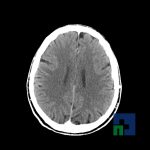

Examinare de rutină cerebrală, nativ și cu substanță de contrast (SDC) pentru diagnosticul:

- Accidentelor vasculare cerebrale ischemice sau hemoragice

- Evaluarea deplasării liniei mediane

- Evaluarea cisternelor perimezencefalice

- Diagnosticul edemului cerebral, a contuziei cerebrale, a leziunilor axonale difuze edematoase/hemoragice, a dilacerării cerebrale, a hematomului intraparenchimatos posttraumatic, a hematoamelor subdurale/extradurale (acute, subacute, cronice), a hemoragiei intraventriculare, a hemoragiei subarahnoidiene